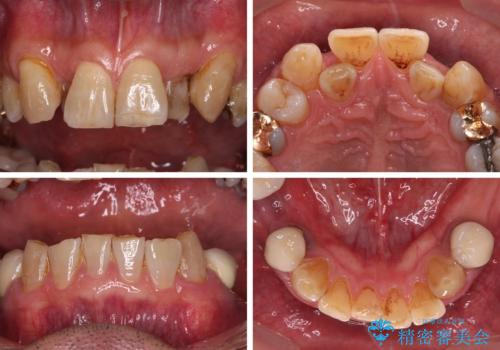

奥歯の欠損と前歯のデコボコを治したい インプラントと矯正治療の総合歯科治療

- 下顎両側の欠損と上顎前歯のデコボコを気にして来院された患者様です。

デコボコは今まで気にせずにいたそうですが、奥歯の欠損改善を機に、矯正治療に興味があるので、相談したいとのことでした。

奥歯に欠損が多く、矯正治療はやや難航することが予想されますが、患者様の希望もあり、上顎左右小臼歯を1本ずつ抜歯し、ワイヤー装置にて矯正治療を行うこととしました。

矯正歯科治療を行うに当たり、痛みや違和感を感じている歯の根管治療を行い、矯正治療中にインプラント埋入し、補綴治療と矯正治療を同時に終了できるように進めて行くこととしました。

銀歯やむし歯治療されている歯を抜歯する治療計画としたため、やや時間はかかりましたが、治療後の仕上がりには大変満足していただけました。